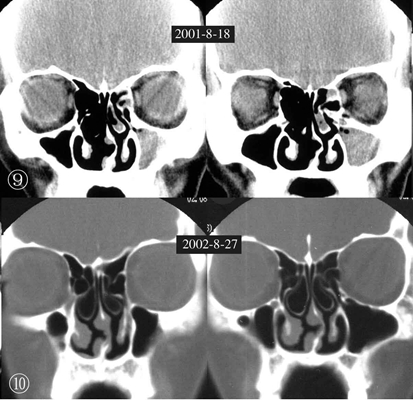

鼻中隔彎曲手術圖解 (43)

鼻中隔彎曲手術圖解 (42)

鼻中隔彎曲手術圖解 (41)